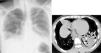

Neumonía lipoidea en un tragafuegos

Acute lipoid pneumonia in a fire-eater